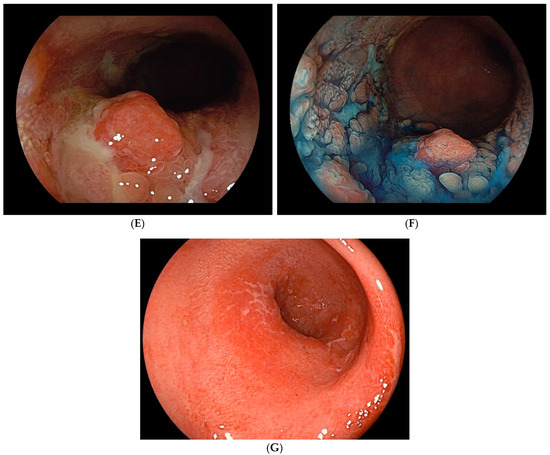

- Sugimoto, S.; Naganuma, M.; Iwao, Y.; Matsuoka, K.; Shimoda, M.; Mikami, S.; Mizuno, S.; Nakazato, Y.; Nanki, K.; Inoue, N.; et al. Endoscopic morphologic features of ulcerative colitis-associated dysplasia classified according to the SCENIC consensus statement. Gastrointest. Endosc. 2017, 85, 639–646. [Google Scholar] [CrossRef]

- Matsumoto, T.; Iwao, Y.; Igarashi, M.; Watanabe, K.; Otsuka, K.; Watanabe, T.; Iizuka, B.; Hida, N.; Sada, M.; Chiba, T.; et al. Endoscopic and chromoendoscopic atlas featuring dysplastic lesions in surveillance colonoscopy for patients with long-standing ulcerative colitis. Inflamm. Bowel Dis. 2008, 14, 259–264. [Google Scholar] [CrossRef]

- Takabayashi, K.; Kato, M.; Sugimoto, S.; Yahagi, N.; Kanai, T. Texture and color enhancement imaging in combination with indigo carmine dye spraying to highlight the border of flat ulcerative colitis-associated neoplasia. Gastrointest. Endosc. 2022, 95, 1273–1275. [Google Scholar] [CrossRef]